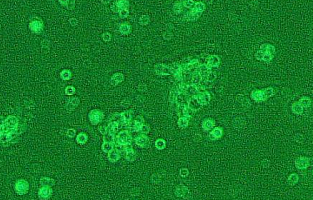

细胞名称:NCI-H2023人非小细胞肺癌细胞

形 态:贴壁;上皮细胞样